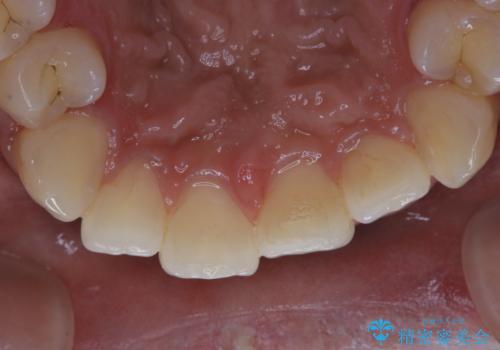

タバコによる着色をPMTCできれいな白い歯に

- タバコによる着色を綺麗にしたいとのことで来院されました。PMTC60分コースを行いました。

PMTCでは、歯の表面の凸凹にミネラルを補給して、ツルツルの表面に仕上げます。定期的にPMTCを行うことにより、歯質の強化になり着色がつきにくい状態になります。

普段の飲食物・歯磨き・生活習慣・喫煙の有無などにより着色の付き具合には個人差があります。どれくらいの頻度で行うことがベストかは、その都度担当の歯科衛生士とご相談します。